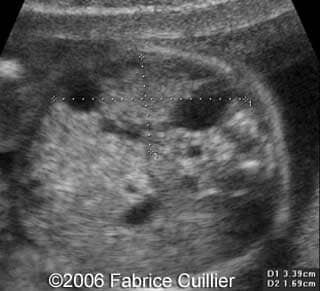

• an abnormal polycystic left kidney (34 X 17 mm) with an abnormal corticomedullar differentiation. This kidney was on the lumbar fossa.

At 24 and 26 weeks, the left kidney lesion had increased. At 34 and 37 weeks, the anomalies were the same. The baby was delivered vaginally (male, 3000 g). At day five, the kidney abnormalities were confirmed. Nevertheless the creatinine level was normal. One month later, a scan revealed a normal right kidney (50 mm) and a left kidney with cysts. The creatinine level was in the normal range. The child was operated (left nephrectomy). The diagnosis of multicystic kidney disease was confirmed.